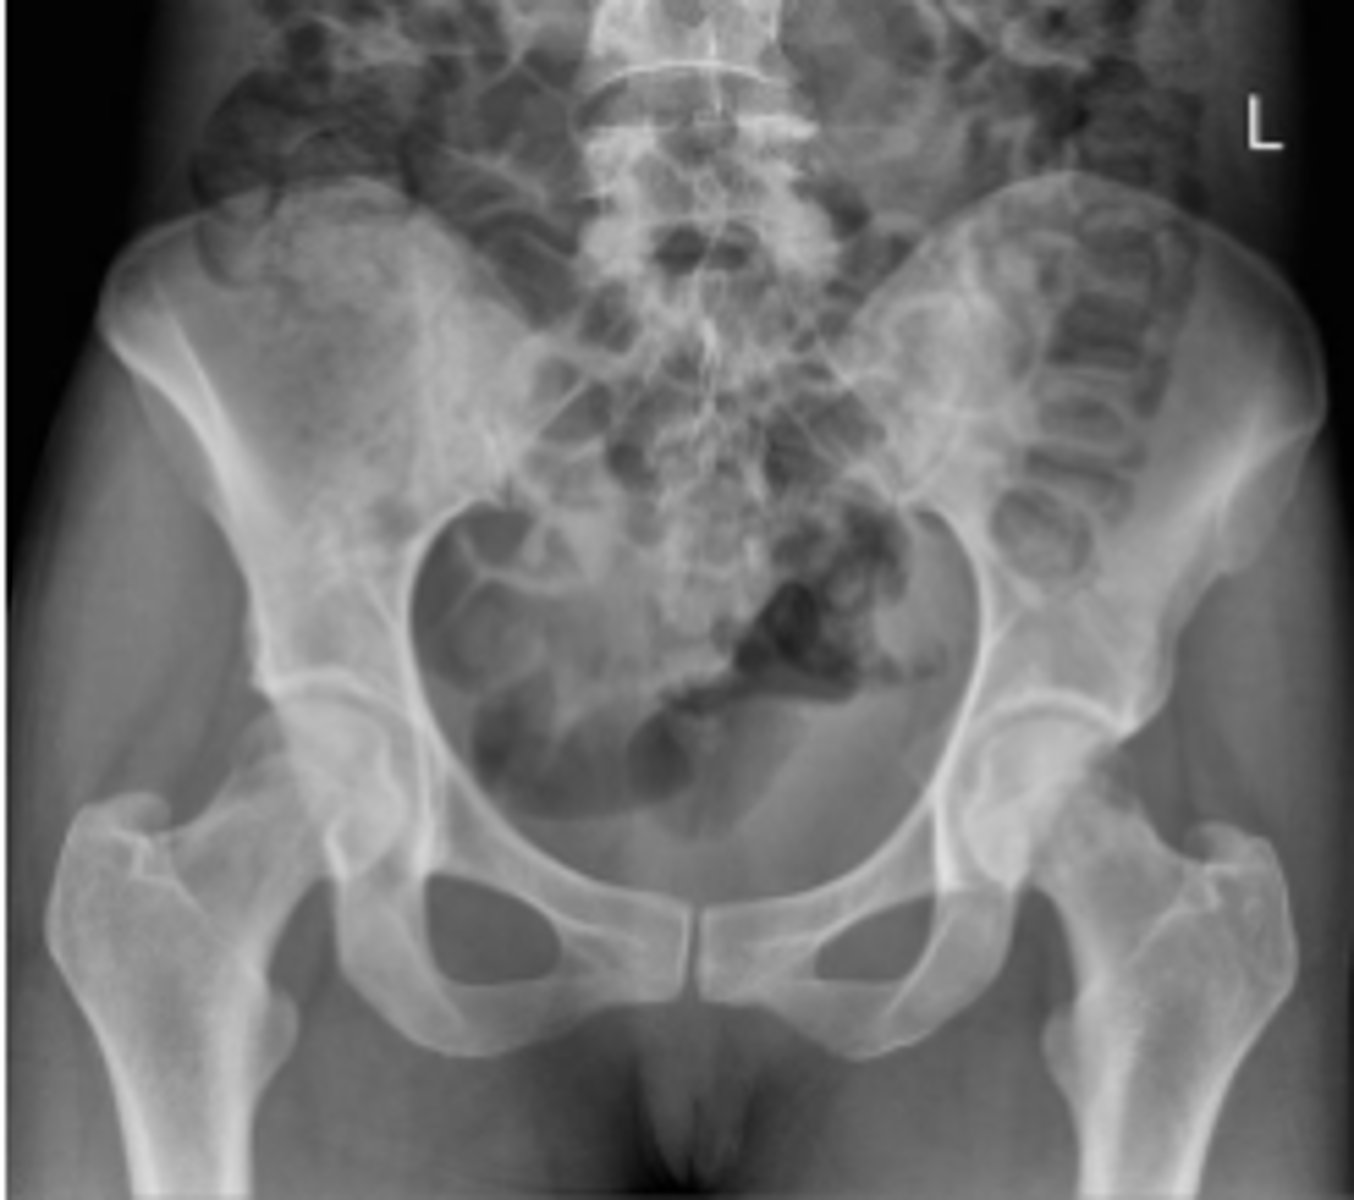

AP pelvis or bilateral hips

What is the name of the radiographic view?